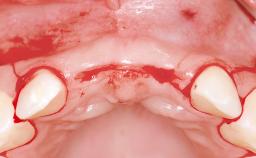

This 20-year-old woman was referred to our department in July 2006. Four months earlier, she had experienced dental trauma to the anterior maxilla when traveling in South America. The emergency treatment included emergency root canal treatment of teeth 12 and 11. Tooth 21 was also subjected to endodontic treatment later. At the initial examination, the patient was not in pain but reported increased mobility of tooth 12. The clinical examination revealed a high smile line, medium thickness of the soft tissue, and rectangular tooth forms. Discoloration of tooth 12 was evident. The periapical radiograph provided by the referring dentist indicated a fracture line at both teeth 12 and 11. A cone-beam computed tomography (CBCT) scan confirmed these fractures. No pathology was found to be associated with tooth 21.

| Bone Volume | Deficient horizontally, allowing simultaneous augumentation |